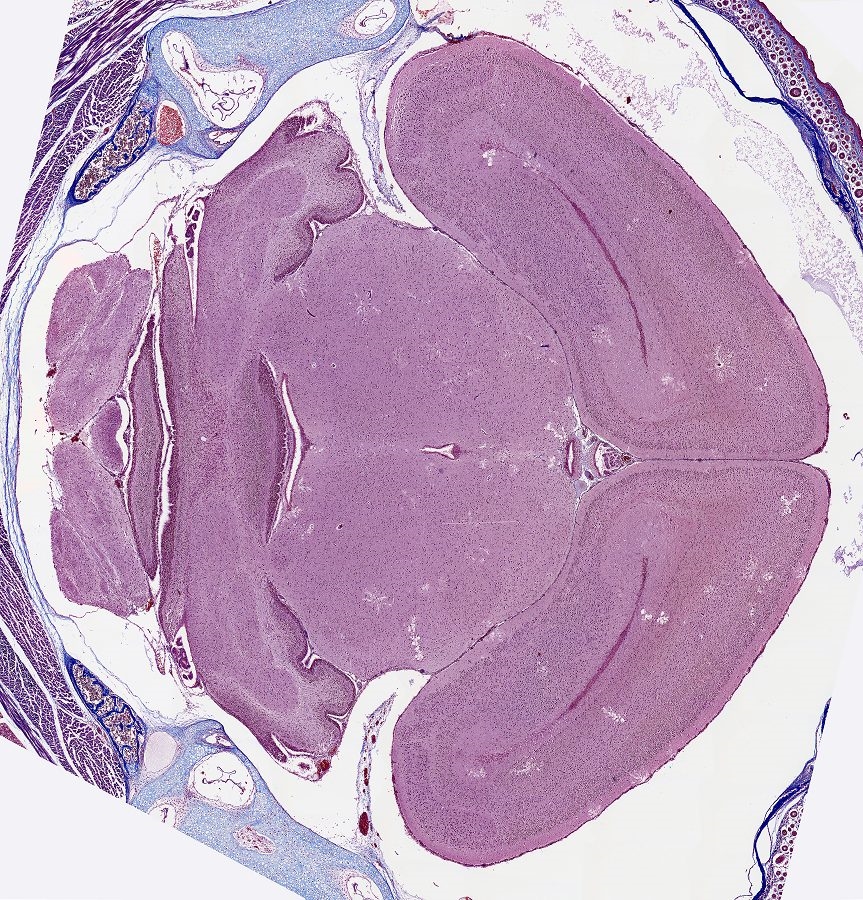

Hier der Hippocampus in mein Gehirnschnitt von eine Junge Maus. Und, es stimmt genau!

Bild ist ein stitch von 34 Bilder. Objektiv Leitz Fluotar 16x.

Ein größeres Bild von 1800x und 2MB ist 'hier' zu downloaden.